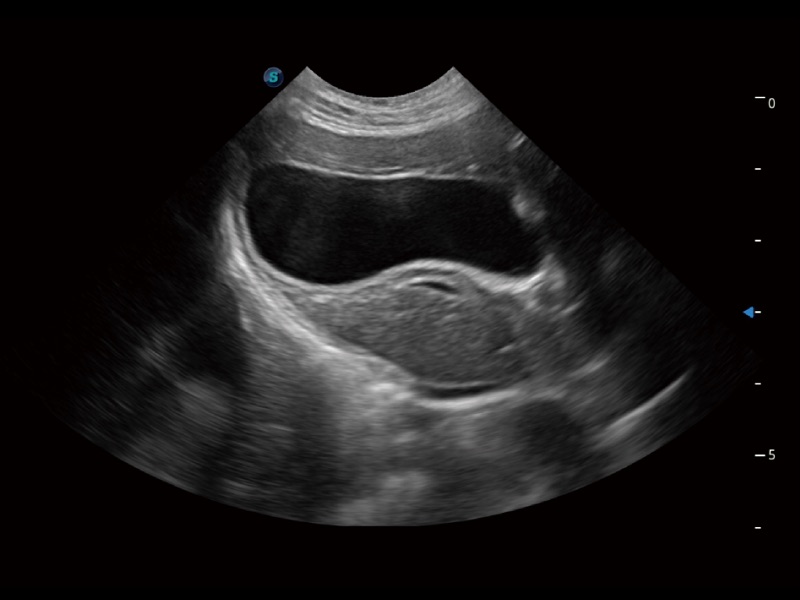

一键自动识别膀胱壁及自动测量膀胱容积,不受膀胱形状和大小的限制,帮助医生快速精准获得测量的数据。

为精细结构及组织边缘提供高清晰度的图像和更大的成像视野。帮助减轻医生的用眼疲劳,快速精准获得测量的数据。